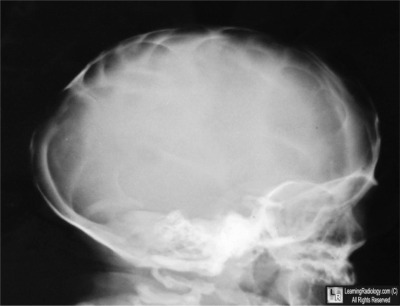

Lateral Radiograph of Skull

4. Lacunar Skull

Lacunar Skull

- Bone dysplasia consisting of multiple oval lucencies separated by dense, bony ridges

- Associated with

- Neural tube defects, especially myelomeningocele

- Chiari II malformation

- Encephalocele

- Not related to degree of concomitant hydrocephalus

- Inner table more affected than outer